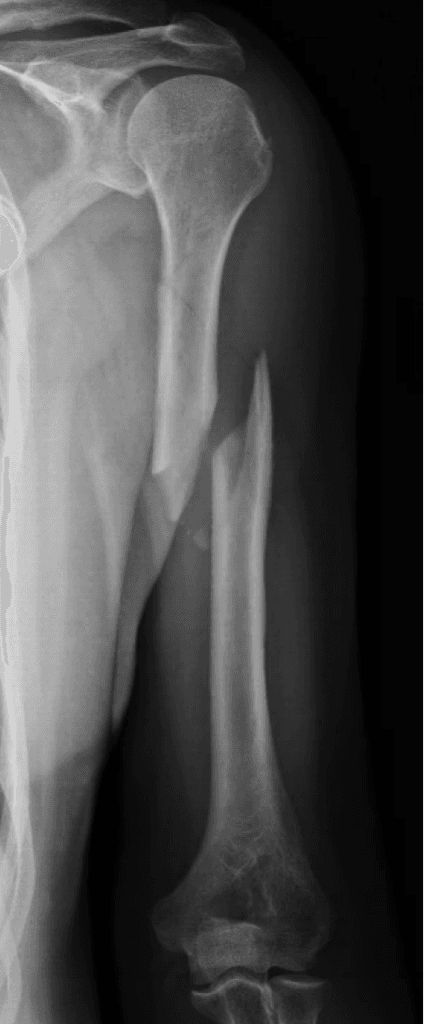

Diaphyseal humeral fractures are breaks in the middle section of the arm bone. These fractures occur from both high-energy trauma in younger people and low-energy falls in older adults.

- X-rays: Standard views to see the fracture.

- AO-OTA Classification: Divides fractures into simple (A), wedge (B), and complex (C) types.